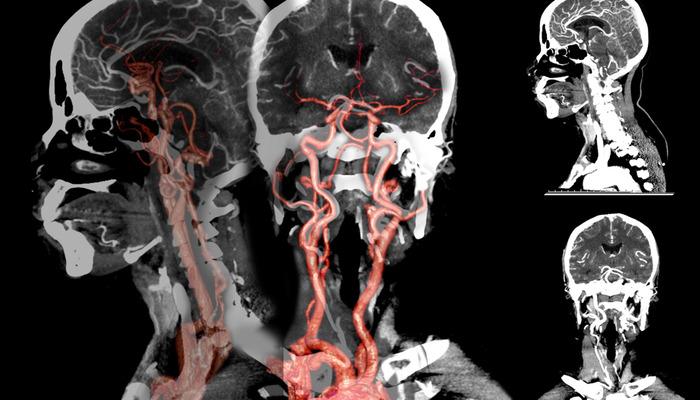

Doç. Dr., beyin kanamasının erkeklerde kadınlara göre daha sık görüldüğünü söyledi. Dr. Çakın, şunları söyledi: “Anevrizmal kanamalar, beyin atardamarlarındaki kabarcıklar nedeniyle meydana gelen beyin kanamaları olarak biliniyor. Özellikle sonbahar ve ilkbahar başlarında bu kanamaların yüzde 10 oranında arttığı gözlendi. Sigaranın etkisiyle beyindeki damarlar tıkanıyor.”

Doç. Dr., beyin kanamasında genetik hastalıkların etkili olabileceğini söyledi. Hakan Çakın, “Yüksek tansiyon, sigara kullanımı ve ileri yaşa bağlı olarak oluşan bu kabarcıklar, mevsimsel döngülerde daha çabuk ortaya çıkıp beyin kanamalarına neden oluyor. Genetik anevrizmalara da daha sık rastlanıyor. Çocukluk döneminde, özellikle Japonya ve Finlandiya'da, ancak “ülkemizde bu kadar yaygın değil. Belli bir yaştan sonra özellikle 30-50 yaş sonrasında hipertansiyon ve sigara kullanımının bu soruna büyük etkisi vardır. At nalı böbrek hastalığı, diyaliz hastalarında ya da tansiyon sorunları ve genetik bozukluklar genç yaşta görülenlerde etkili olabiliyor” dedi.